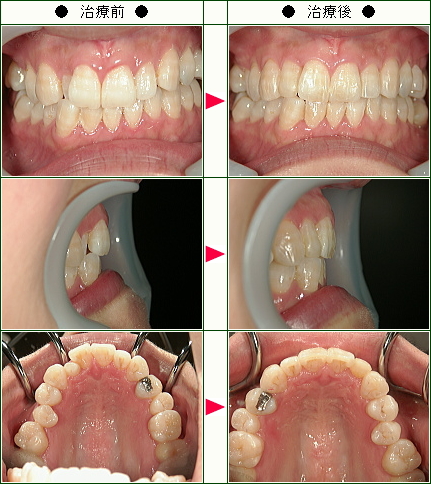

☆歯のデコボコ矯正症例(M.Y様 26歳 男性)